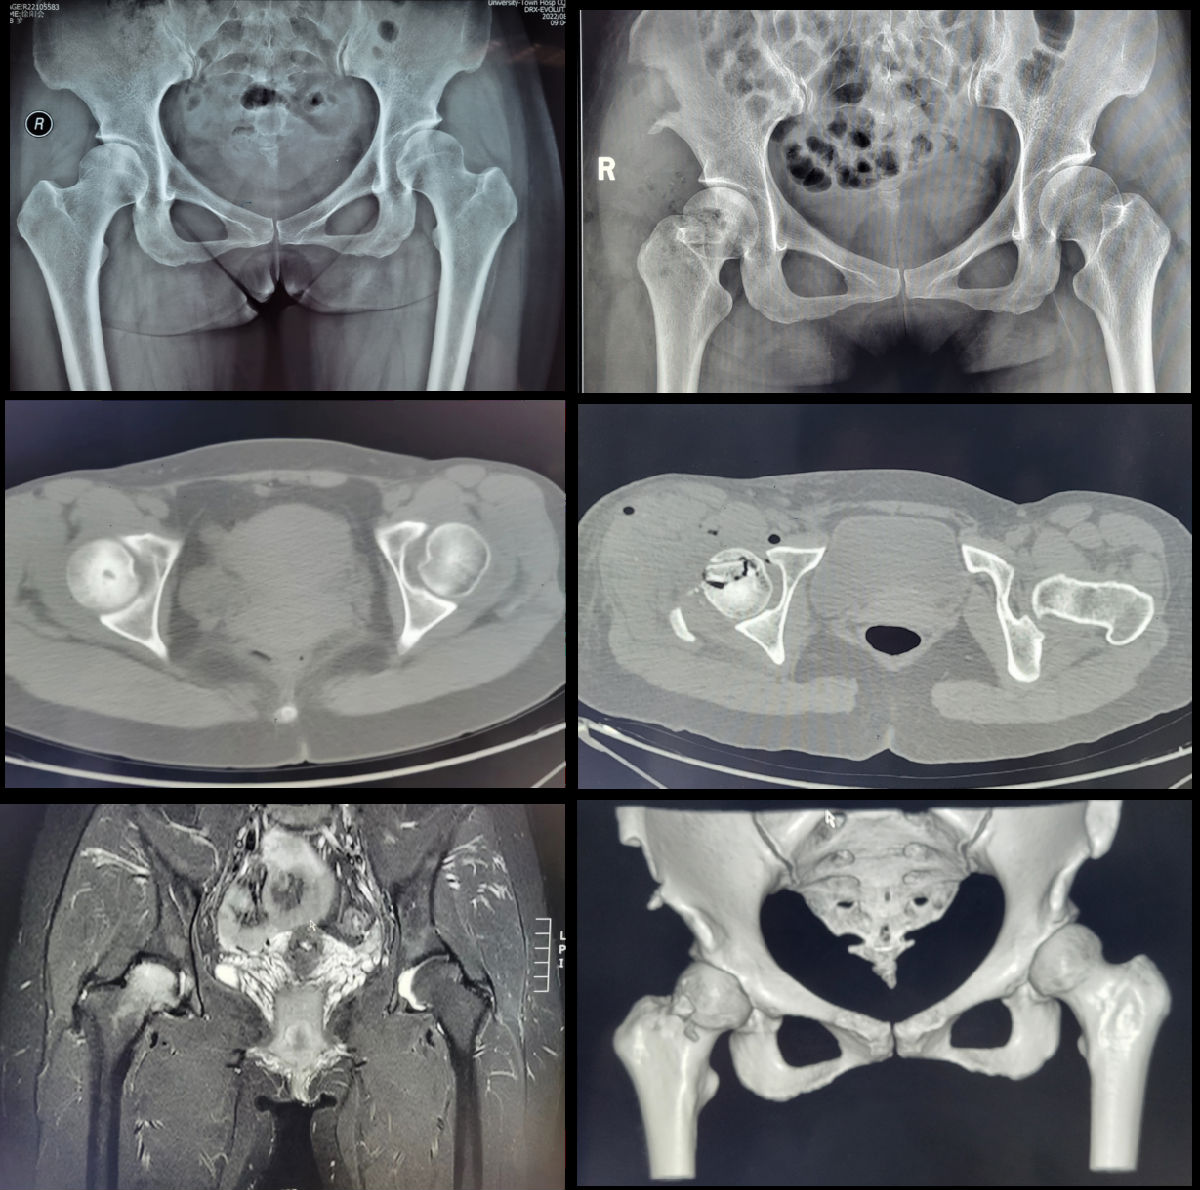

典型病例:女性患者,39岁,因“右侧髋部疼痛、活动受限6月”入院,诊断右侧股骨头坏死 Ficat分期IIB期;于我院骨科在全麻下行保髋治疗(股骨头带血管蒂髂骨瓣移植术)。术后成功缓解疼痛并挽救股骨头,延缓股骨头坏死进展。

1.股骨头带血管蒂髂骨瓣移植术